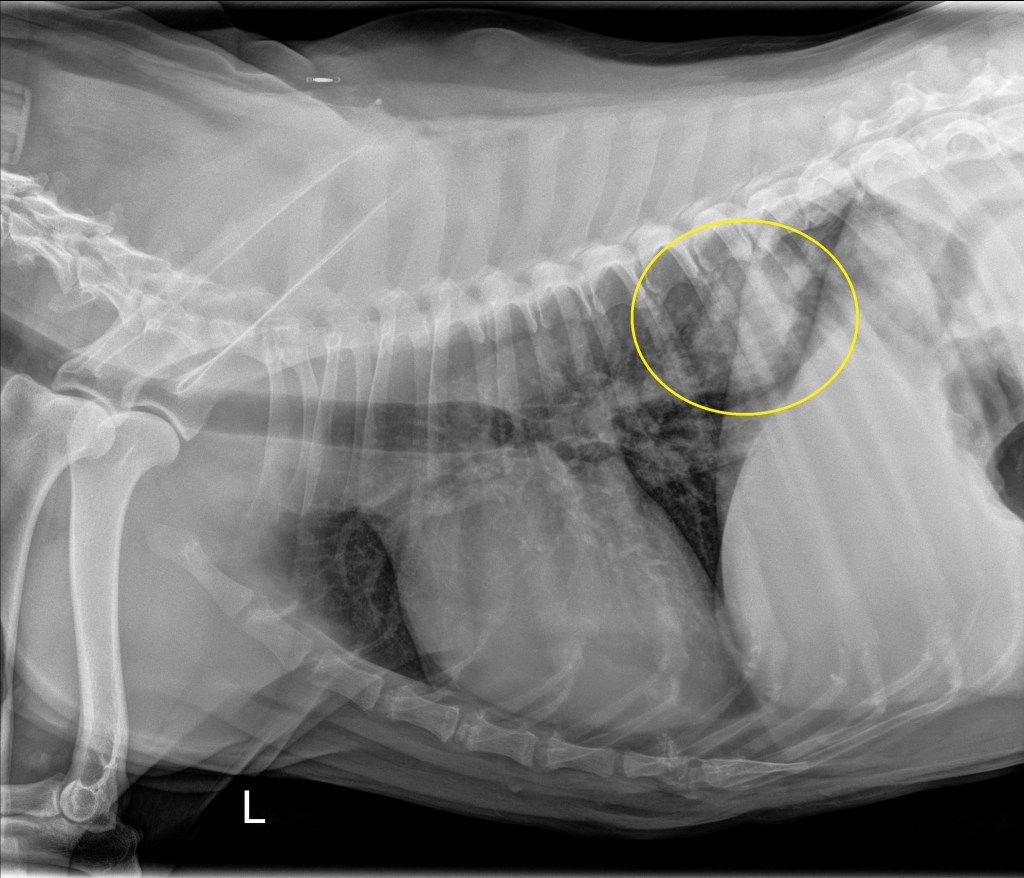

Thoracic radiographs: A mildly ill defined ovoid ~5.0 x 5.3 cm soft tissue opaque mass is located in the dorsal aspect of the right caudal lung lobe in the 7th-10th intercostal spaces. No evidence of intrathoracic lymphadenopathy. Concurrent mild bronchial and interstitial pattern throughout the lungs (likely an age appropriate finding). Findings consistent with primary (e.g. carcinoma) or slightly less likely metastatic or multicentric (e.g. lymphoma) pulmonary neoplasia. Much less likely differentials include granuloma secondary to fungal disease (patient lives in the northeast portion of the country with no travel history) or parasitic infection.